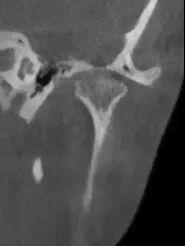

治疗后1

3个月复诊时,CBCT显示,晓涵的髁突骨质磨损的区域已经开始修复,张嘴幅度恢复正常,弹响也几乎消失了。顾女士看着报告松了口气:“没想到‘戴个牙套’就能把骨头养回来!”目前晓涵情况稳定,现在正在进行后续的牙齿矫正,让排列不齐导致咬合不好的牙齿慢慢长到正常位置。